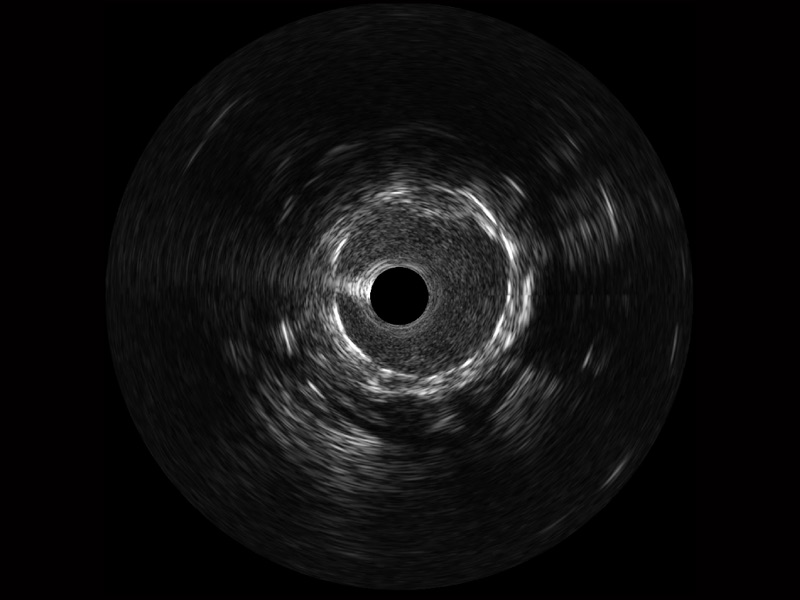

MILE米乐集团官网宽频IVUS图像

传统IVUS图像

对比传统IVUS导管成像,MILE米乐集团官网宽频IVUS图像的近场支架梁显影更细腻,远场中膜外血管仍清晰可辨,兼顾远中近,兼顾分辨力与穿透深度